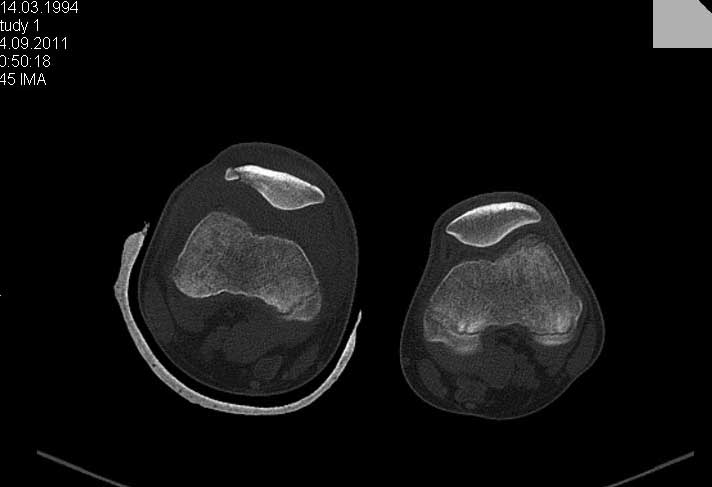

Перелом надколенника.

Обратился ребёнок 15 лет с оскольчатым переломом надколенника. Давность травмы 1 неделя.Поделитеся пожалуйста опытом.

Показанием к оперативному лечению перелома надколенника у подростков есть внутрисуставное смещение отломков больше 3 мм.